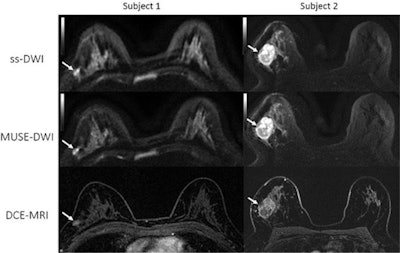

The future of DWI-MRI for breast imaging may not be far off, either. In May, researchers detailed how they repurposed a DWI-MRI protocol originally designed for brain imaging. The multiplexed sensitivity-encoding (MUSE) protocol resulted in better image quality and improved signal-to-noise ratio for breast lesions.

"MUSE DWI yielded significantly improved image quality compared with single-shot DWI in phantoms and participants," the team wrote.